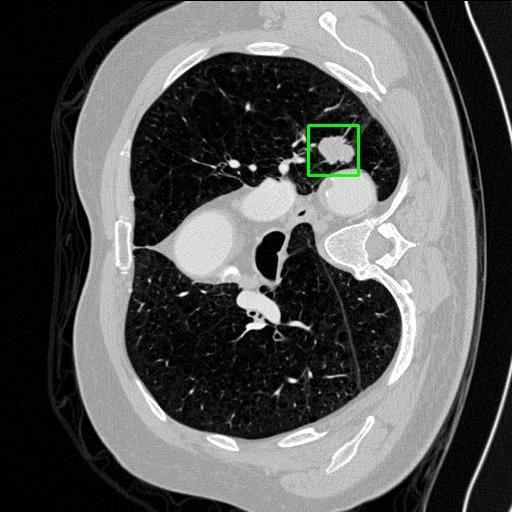

We developed an AI-based system using deep learning models for analyzing lung CT scans to detect and classify pulmonary nodules. We chose the YOLOv11 architecture for its enhanced object detection capability and adapted it specifically for medical imaging, incorporating pixel-level precision and severity classification.

Classification into three severity levels with colored bounding boxes.

Maintaining performance on small, complex features like micro-nodules tested the limits of traditional object detectors.

Designed a severity classification system that categorizes nodules into null, moderate, and severe using colored bounding boxes, assisting in rapid clinical decision-making.